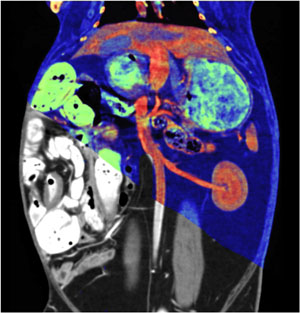

"With DECT, structures with different atomic make-up, such as iodine, calcium and dense blood or metal, are vividly differentiated," said Dr. Yeh at the RSNA 2019 Annual meeting. "Even when objects have identical HU on a regular CT, with DECT different materials appear like different colors."

Dual-energy CT (DECT) image

The benefits of these different colors, aka "color vision," makes DECT a transformative technology in daily clinical practice. Dr. Yeh explains that radiologists routinely encounter ambiguous lesions at CT in their daily practice. Since many types of materials may have similar HU values, it is hard to tell whether a lesion is enhancing, calcified or hemorrhagic. DECT shows radiologists what the underlying atoms are and readily differentiates among such entities.